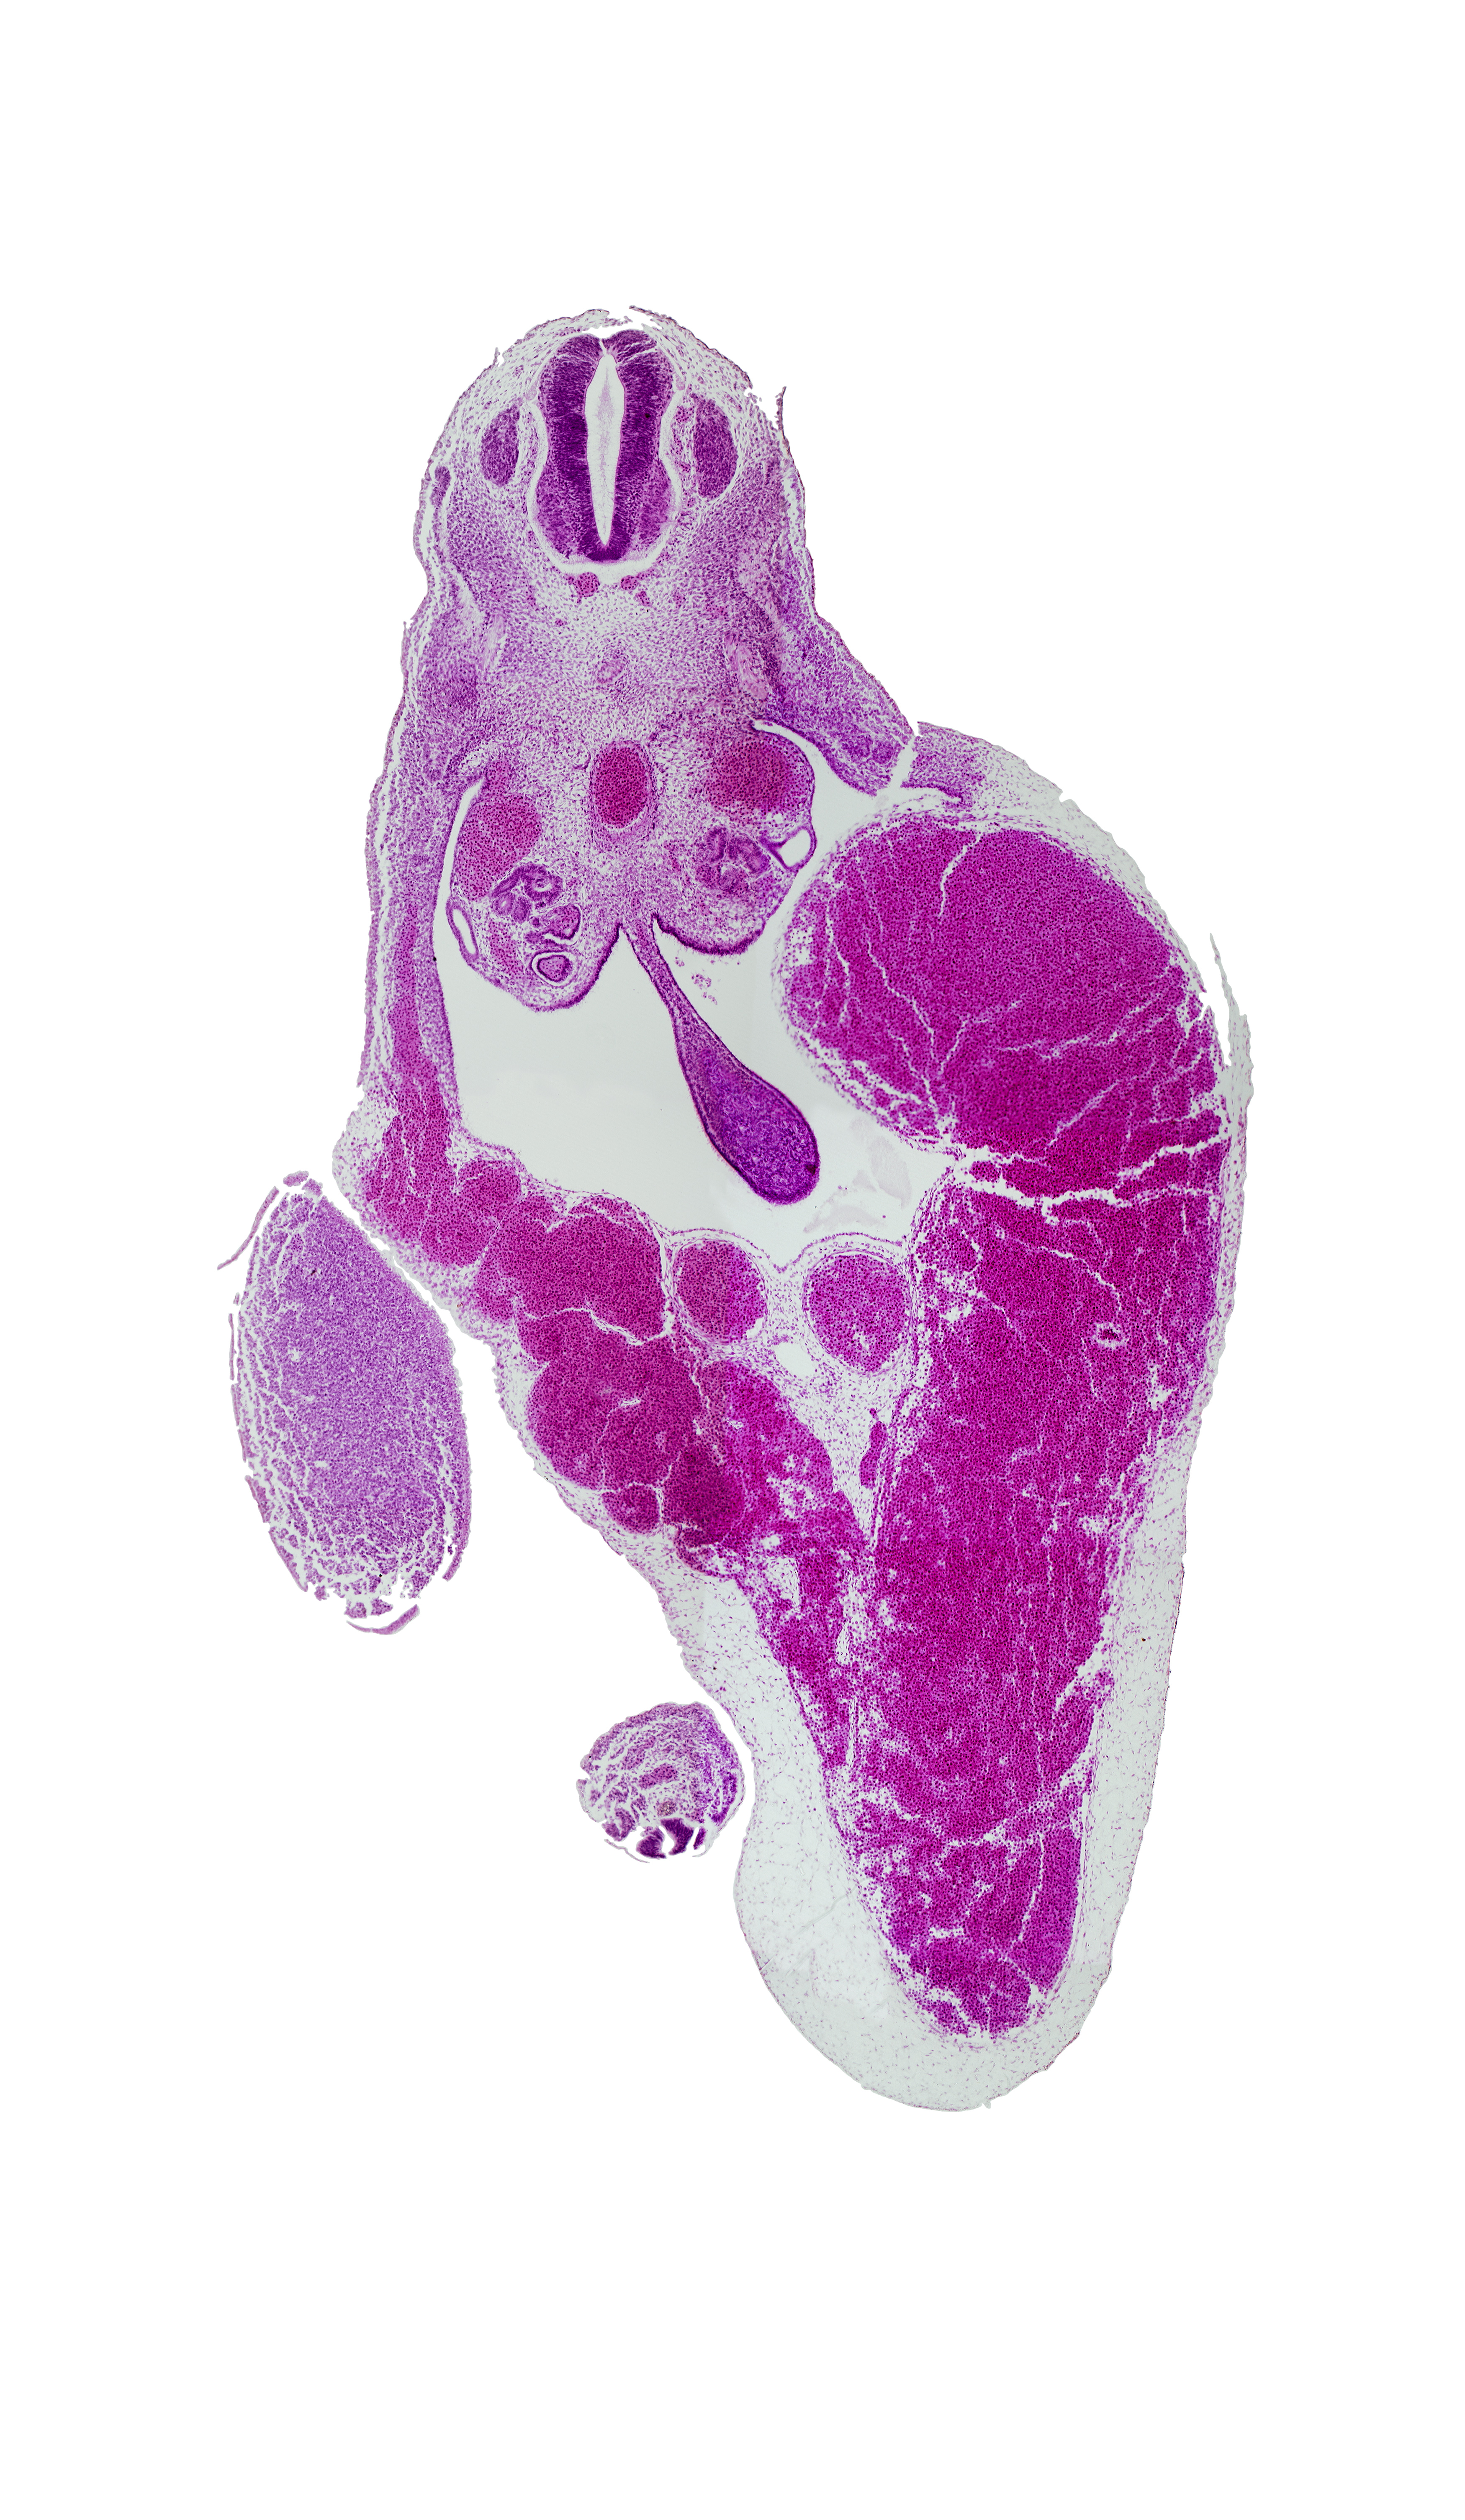

Carnegie Embryo #721 | Location: 22-01-05

Keywords: T-9 spinal ganglion, aorta, caudal eminence, common umbilical vein, dermatomyotome, dorsal mesentery, gonadal ridge, junction of umbilical veins, left umbilical vein (congested), mesonephric duct, midgut, peritoneal cavity, rib primordium, right umbilical vein, umbilical cord

Source: The Virtual Human Embryo.